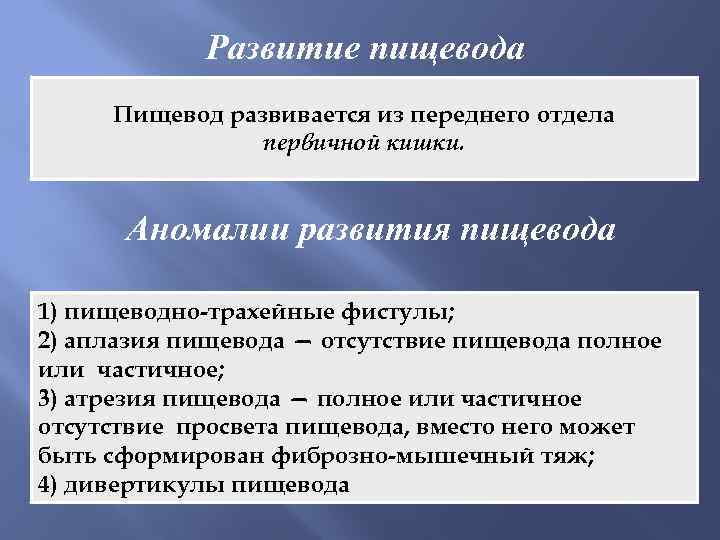

Развитие пищевода Пищевод развивается из переднего отдела первичной кишки. Аномалии развития пищевода 1) пищеводно-трахейные фистулы; 2) аплазия пищевода — отсутствие пищевода полное или частичное; 3) атрезия пищевода — полное или частичное отсутствие просвета пищевода, вместо него может быть сформирован фиброзно-мышечный тяж; 4) дивертикулы пищевода

Развитие пищевода Пищевод развивается из переднего отдела первичной кишки. Аномалии развития пищевода 1) пищеводно-трахейные фистулы; 2) аплазия пищевода — отсутствие пищевода полное или частичное; 3) атрезия пищевода — полное или частичное отсутствие просвета пищевода, вместо него может быть сформирован фиброзно-мышечный тяж; 4) дивертикулы пищевода